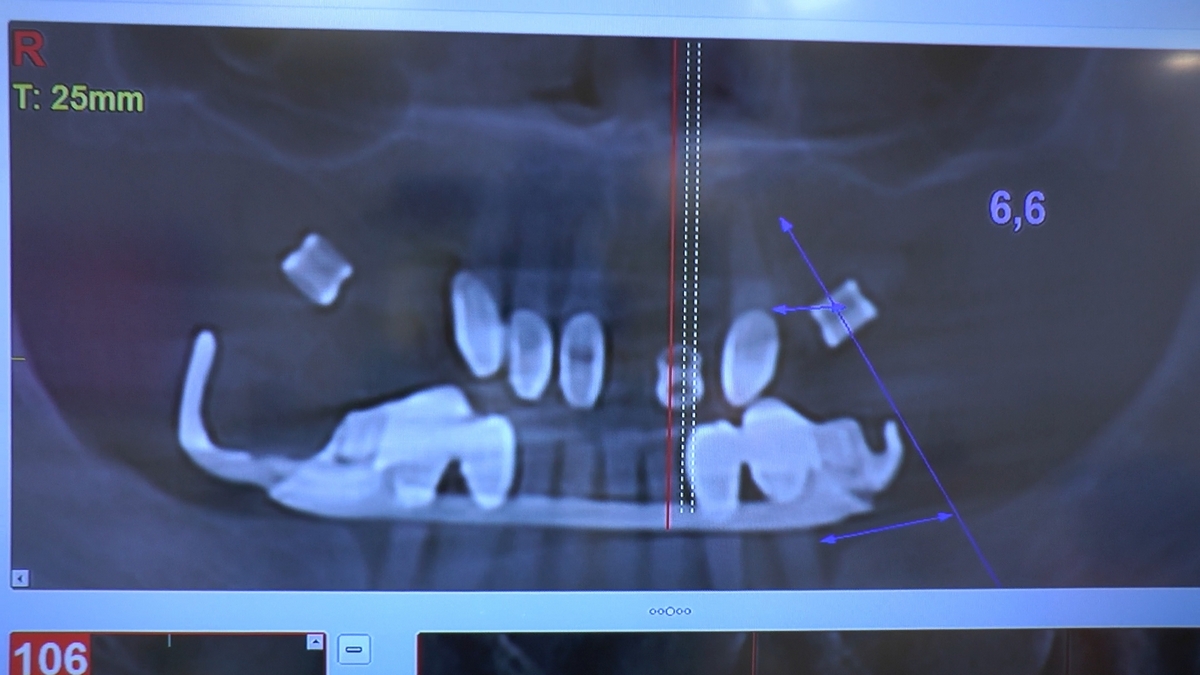

W trakcje dwóch dni zabiegowych, piątek i sobota, 5 i 6 października 2018 roku, lekarze uczestniczący w 6 Sesji VI Sezonu, wykonali wiele zabiegów o wysokim stopniu trudności. Przeprowadzili je pod kierunkiem Mentorów Instytutu Vivadental – dr n.med. Violetty Szycik, dr n.med. Magdaleny Kisłowskiej-Syryczyńskiej oraz dr Małgorzaty Piotrowskiej.

Wprowadziliśmy łącznie 25 implantów w tym wykonaliśmy:

dwa zabiegi All- on -4 / jeden w szczęce, jeden w żuchwie/ z usunięciem zębów i natychmiastową implantacją oraz natychmiastową odbudową protetyczną